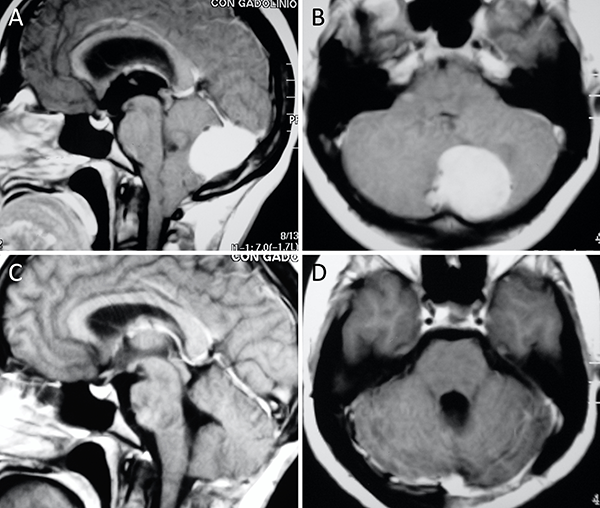

Figura 4. Meningioma petro-clival. A-B: RM preoperatoria; C-D: RM postoperatoria.